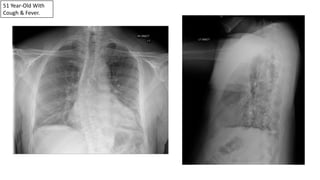

51 Year-Old With

Cough & Fever.

Pneumonias Can Be Subtle On The PA View Alone.

Retrocardiac LLL Pneumonia On The Lateral View